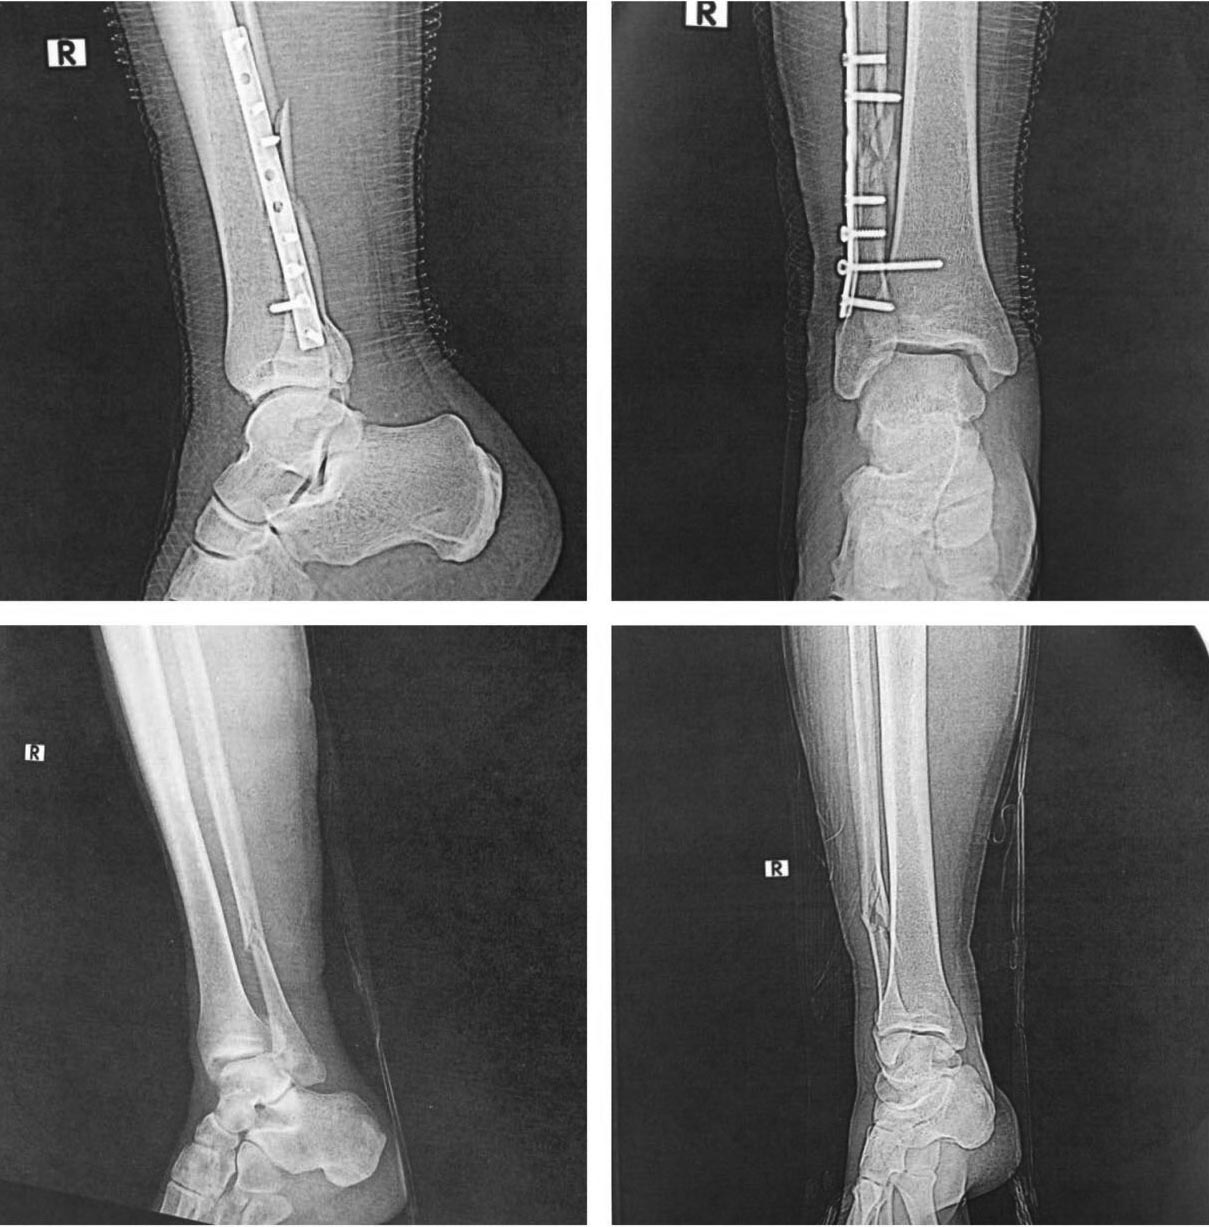

Мне кажется сращение малоберцовой состоялось, межберцовый диастаз сомнителен, задний край большеберцовой клинически незначим. Укорочение малоберцовой кости не менее 3 мм.

1. Для определения длинны м/б кости нужна третья проекция (mortise).

АНДРЕЙ Хочется уточнить механизм травмы и нельзя ли выполнить рентгенографию в четких проекциях с центрацией луча на сустав. На последней прямой две голени в разных проекциях. Возможно ситуация не столь критическая. Да и на первых снимках подвывиха не было, и пациент ходил без опоры

На снимочках до и после. Если после представленный снимок сразу после операции-то там уже явный подвывих кнаружи.Причина по-моему в том, что малоберцовая кость не адаптирована полностью в сулкусе синдесмоза ,а ротирована и в таком положении стянута винтом.Так что єтап зачистки рубцов в пространстве синдесмоза обязателен.Ну и фиксация с усранением ротации малоберцовой кости 2-мя винтами.